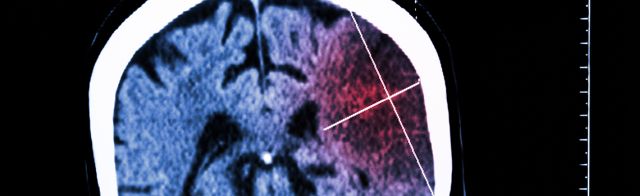

Neue MRT-Technik in der Universitätsmedizin Mainz erkennt Schlaganfälle in kürzester Zeit

Stiftungen fördern Schlaganfallforschung am UKE mit bis zu 2,75 Millionen Euro

Tenecteplase bei Schlaganfällen nach Perfusionsbildgebung

Bessere Ergebnisse nach endovaskulärer Thrombektomie bei akutem Basilaris-Verschluss

‚Botox‘ nach Schlaganfall: Empfohlene Behandlung gegen Spastik viel zu selten angewandt

Bahnbrechende Erkenntnisse geben Hoffnung auf schnellere und bessere Genesung nach einem Schlaganfall